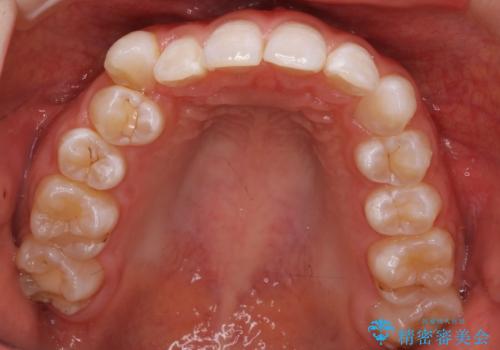

- 右上の八重歯と歯のデコボコ、そして上下の歯の中心(正中)のズレを気にされて来院されました。精密な検査の結果、歯が並ぶスペースが不足しているため、上顎の小臼歯(前から数えて4番目の歯)を抜歯し、そのスペースを利用して歯並び全体を整える治療計画を立案しました。これにより、八重歯の位置を適切に改善し、叢生(歯のデコボコ)を解消するとともに、上下の正中線のズレも改善することを目指します。

今回の矯正治療では、歯が並ぶスペースを確保するため、上顎の小臼歯を抜歯しました。抜歯によってできたスペースを有効活用し、ワイヤーやブラケットを使って右上の八重歯を適切な位置へ移動させ、叢生を解消していきました。また、治療を通じて上下の歯の中心である正中線のズレも改善するよう、慎重に歯を動かしました。治療の結果、長年気にされていた八重歯と歯のデコボコが解消され、上下の正中線も一致。機能的にも審美的にもバランスの取れた、美しい歯並びと笑顔を獲得していただけました。